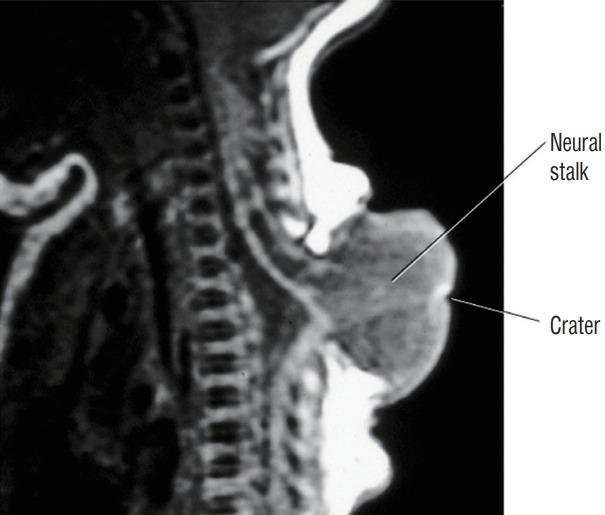

Spinal dysraphic lesions due to focal nondisjunction in primary neurulation are commonly encountered in paediatric neurosurgery, but the "fog-of-war" on these conditions was only gradually dispersed in the past 10 years by the works of the groups led by the senior author and Prof. Kyu-Chang Wang. It is now clear that limited dorsal myeloschisis and congenital spinal dermal sinus tract are conditions at the two ends of a spectrum; and mixed lesions of them with various configurations exist. This review article summarizes the current understanding of these conditions' embryogenetic mechanisms, pathological anatomy and clinical manifestations, and their management strategy and surgical techniques.

由于原发性神经管形成过程中的局灶性不分离导致的脊柱裂病变在小儿神经外科中很常见,但在过去10年中,由资深作者和王宇辰教授领导的团队的工作才逐渐驱散了这些病症上的“战争迷雾”。现在已经明确,有限性背侧脊髓裂和先天性脊柱皮样窦道是同一谱系两端的病症;并且存在各种形态的它们的混合病变。这篇综述文章总结了目前对这些病症的胚胎发生机制、病理解剖和临床表现,以及它们的治疗策略和手术技术的认识。